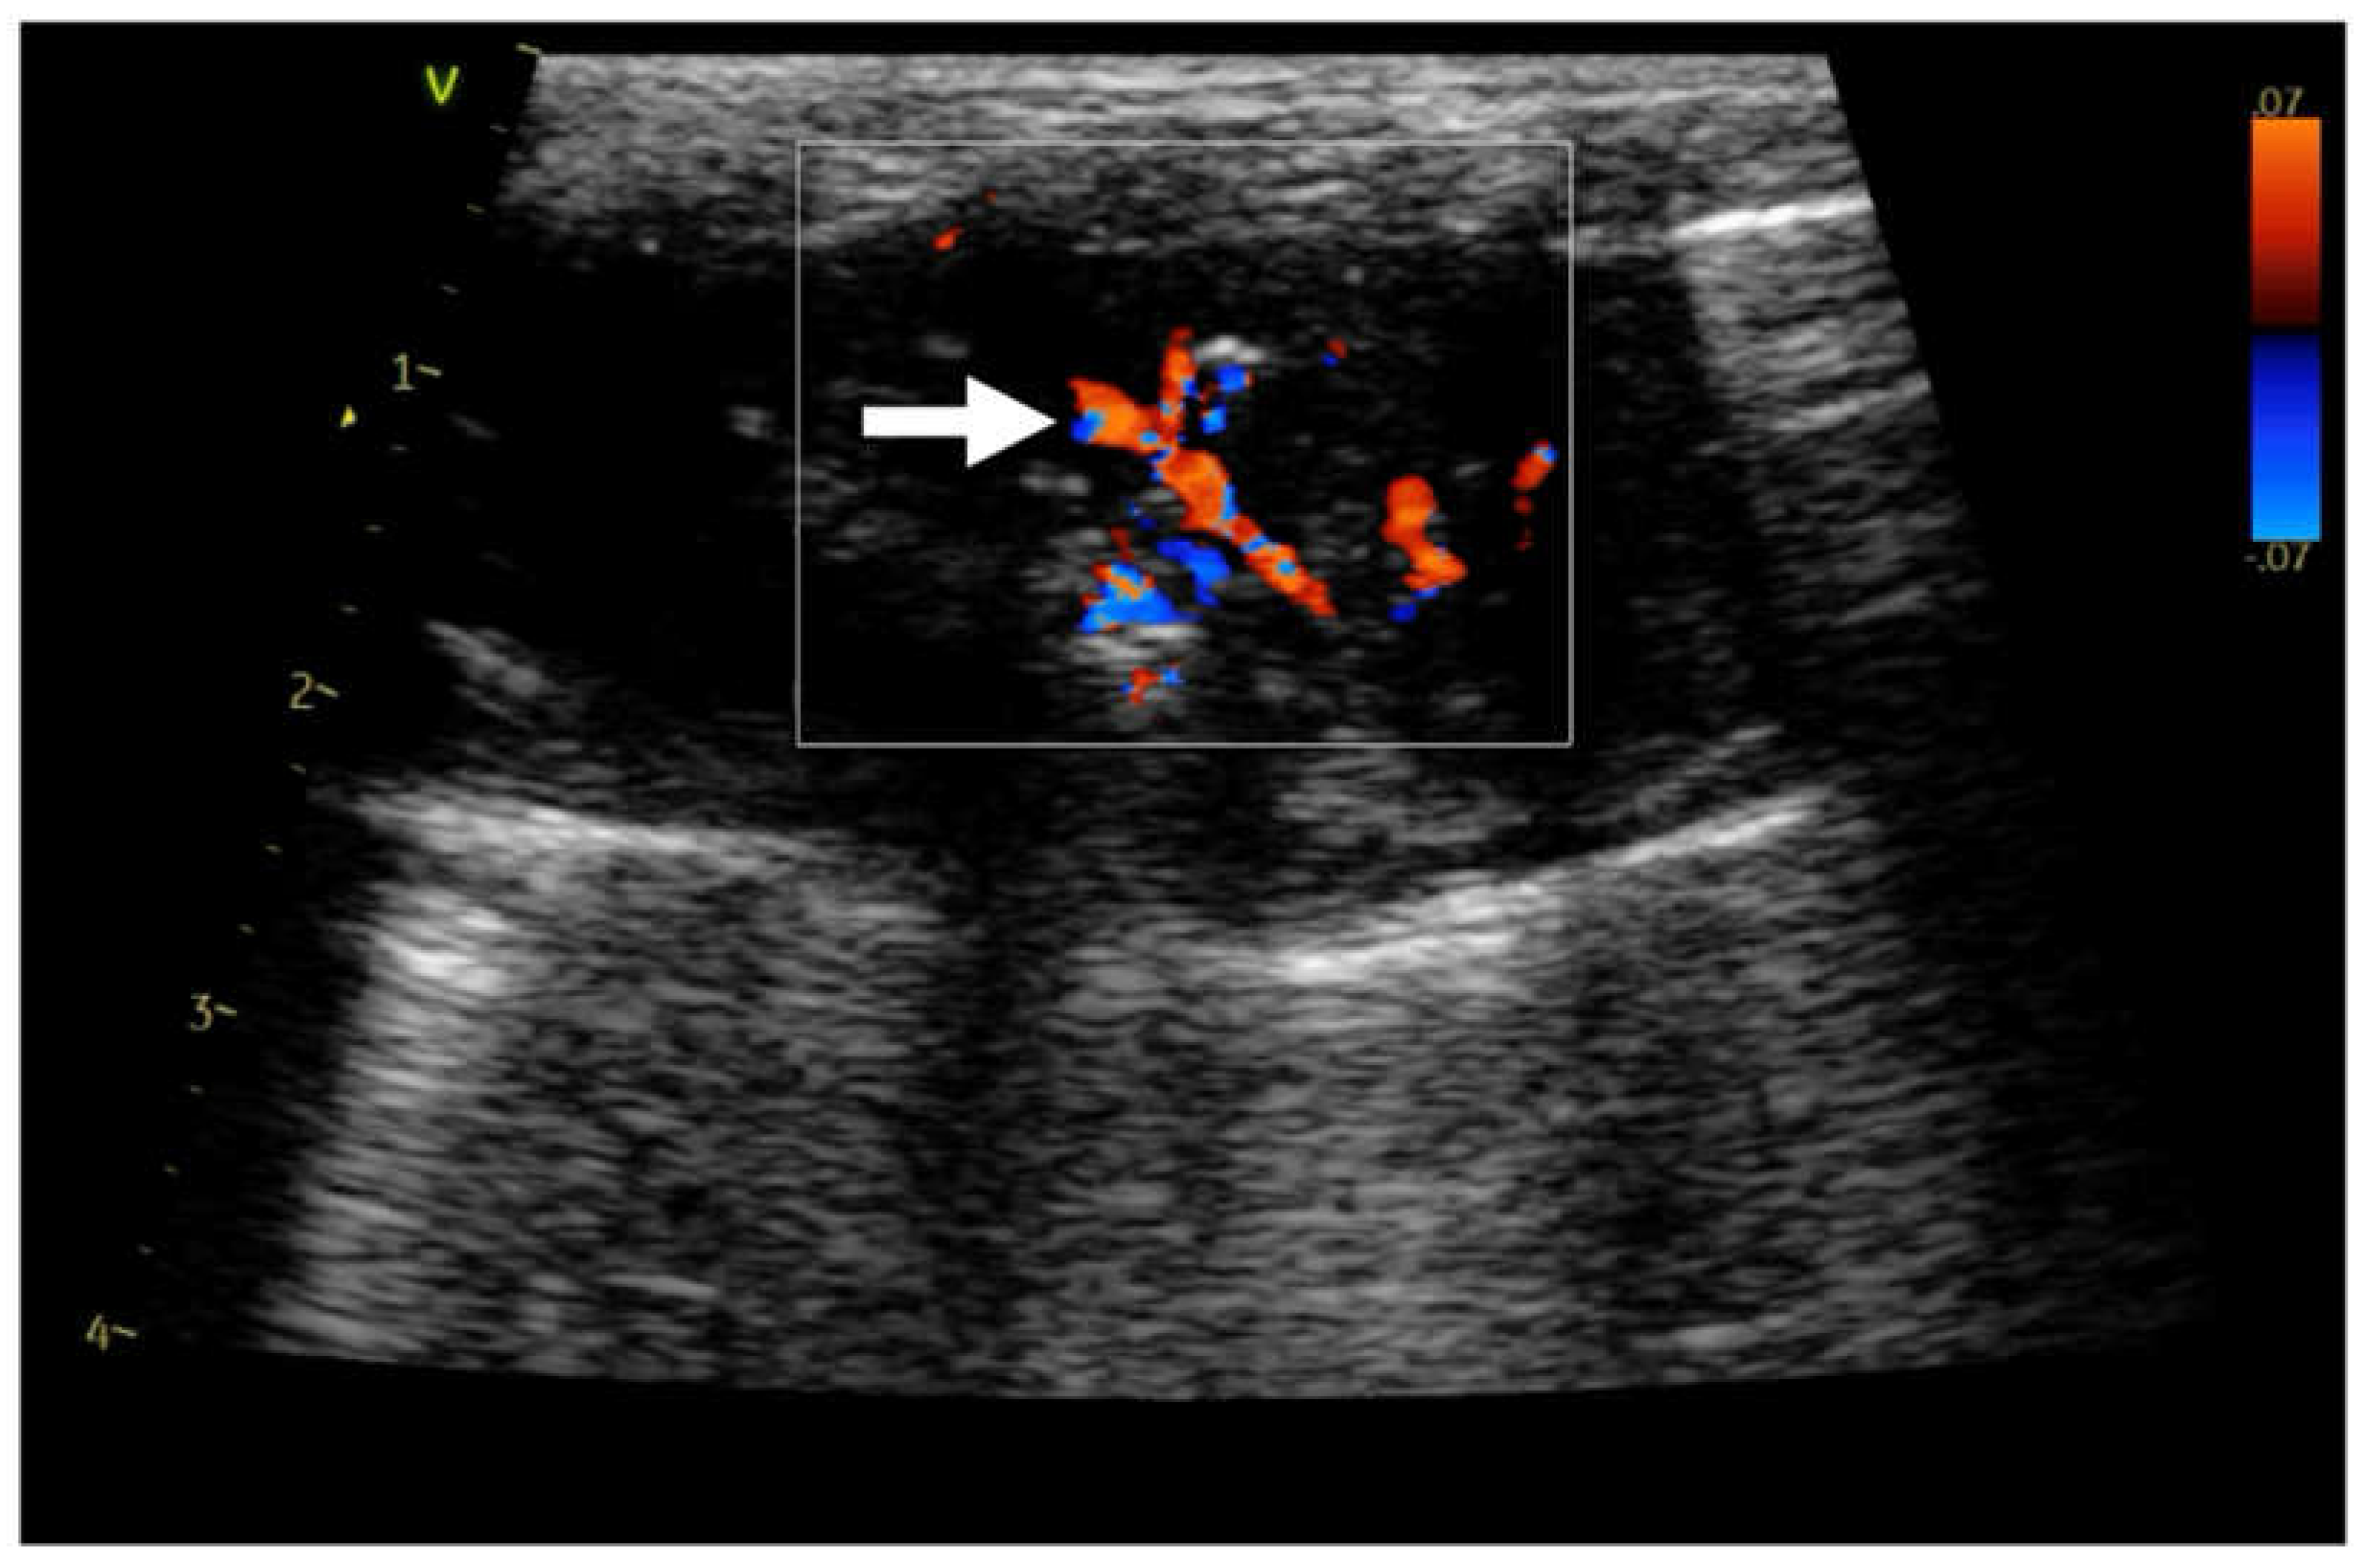

| CD | color doppler | |

| Hv | chaotic type vascularity | |

| Pv | penetrating type vascularity | |

| Rv | residual type vascularity | |

| Tv | tree-like vascularity | |